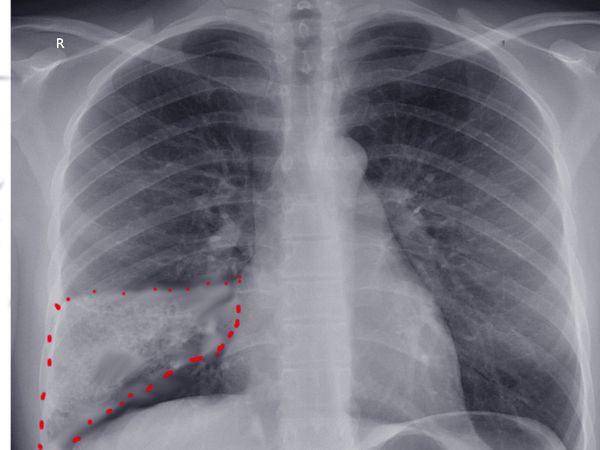

2. Рентгенография органов грудной клетки. Рентгенологические признаки инфаркта лёгкого и его осложнений можно увидеть, начиная со 2–5-х суток после возникновения закупорки лёгочной артерии. Инфаркту лёгкого могут предшествовать такие признаки ТЭЛА:

Признаки инфаркта появляются по мере нарастания повреждения сосудистых стенок с выхождением крови в лёгочную ткань и просвет альвеол [2]. Инфаркт на снимке выглядит как тень, чаще она определяется в нижней доле лёгкого, рядом с плеврой, вблизи междолевой щели, так как именно здесь он обычно возникает.

Форма инфаркта лёгкого в разных проекциях отличается: во фронтальной проекции (как бы спереди) она треугольная, ромбовидная или трапециевидная, а в боковой — округлая или овальная. Структура тени инфаркта лёгкого чаще однородная, интенсивность её зависит от размеров инфаркта, стадии процесса и присоединившихся осложнений (пневмония, распад и др.). Для неосложнённого инфаркта лёгкого характеры чёткие, ровные или волнистые контуры. Изменение структуры тени и её контуров может свидетельствовать о присоединении осложнений [2][9][11].

![Клиновидный инфаркт лёгкого на рентгенограмме грудной клетки [8] Клиновидный инфаркт лёгкого на рентгенограмме грудной клетки [8]](/media/bolezny/infarkt-legkogo/klinovidnyy-infarkt-lyogkogo-na-rentgenogramme-grudnoy-kletki-8_s.jpeg?dummy=1758613643916)

Клиновидный инфаркт лёгкого на рентгенограмме грудной клетки [8]